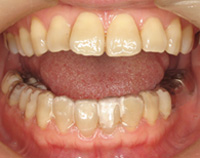

2) 矯正中の状態

叢生(そうせい…歯がデコボコしたり、重なりあって生えていたりする状態)

開咬(かいこう…奥歯はしっかり噛んでいるが、上下の前歯が噛まずに隙間がある状態)